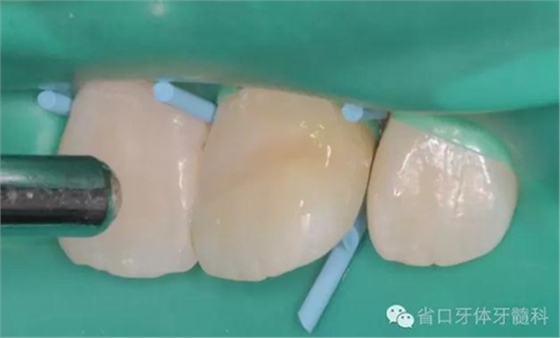

斷冠粘接前試對接

DUO-LINK樹脂水門汀(BISCO)對位粘接,(牙齦紅腫,沒有安放橡皮障)

光固化,去除多余樹脂水門汀,近中鄰面洞和舌側開髓孔樹脂充填,拋光,調整咬合。

橡皮障隔濕后酸蝕,

涂布粘接劑,光照

瓷納美樹脂(Densply)分層充填,

逐級拋光。